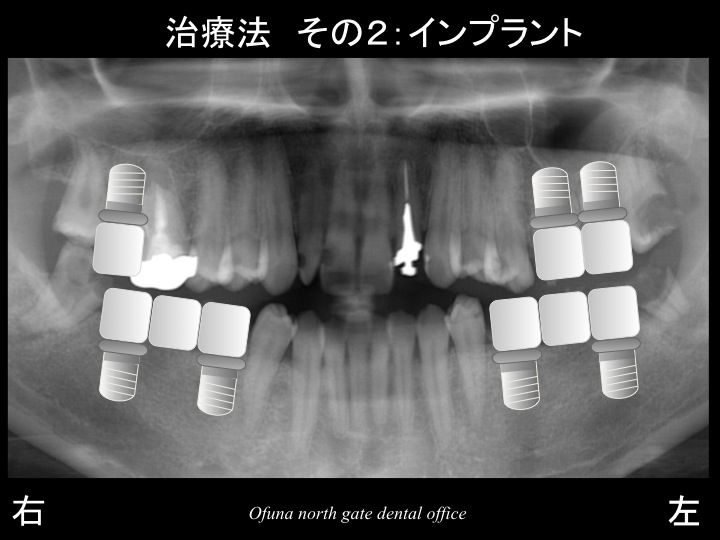

先程の×印を抜歯した場合には、以下の2つの治療方法が考えられます。

固定式であるインプラント治療を希望されました。

最終的な治療は以下になりました。

下顎は、左右とも2本のインプラントで3歯分を作製するブリッジ、

上顎は、左右ともに天然歯によるブリッジです。

このブリッジはもちろん保険で行います。